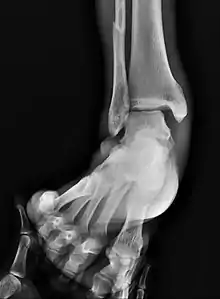

| Fracture of both sides of the ankle with dislocation as seen on anteroposterior X-ray. (1) fibula, (2) tibia, (arrow) medial malleolus, (arrowhead) lateral malleolus | |

On X-rays, there can be a fracture of the medial malleolus, the lateral malleolus, and/or of the anterior/posterior margin of the distal tibia. The posterior margin (known as the posterior malleolus) is much more frequently injured than the anterior aspect of the distal tibia. If both the lateral and medial malleoli are broken, this is called a bimalleolar fracture (some of them are called Pott's fractures). If the posterior malleolus is also fractured, this is called a trimalleolar fracture.